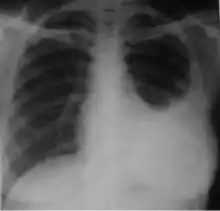

4. Pleural effusion - Presence of a significant amount of fluid within the pleural space. This finding must be distinguished from blunting of the costophrenic angle, which may or may not represent a small amount of fluid within the pleural space (except in children when even minor blunting must be considered a finding that can suggest active TB).

-

Chest x-ray showing dense opacity pleural effusion in the lower left lung of primary pulmonary TB.